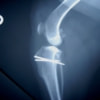

■ 症例20 ポメラニアン 8ヶ月 1.8kg

左右膝蓋骨脱臼 グレードⅢ

2ヶ月前から間欠的跛行が認められ、両膝の膝蓋骨脱臼整復術を行った。

手技は縫工筋及び内側広筋の解放、脛骨粗面の外側転位、滑車ブロック形造溝術、内外側関節包の縫縮を選択し実施した。

右側の膝蓋骨脱臼は上記手技で整復されたものの、左側はそれのみでは膝蓋骨が浮く様子が認められた。その為、PDS縫合糸にて膝蓋靱帯を1糸のみ縫合し、靱帯の縫縮を行った。